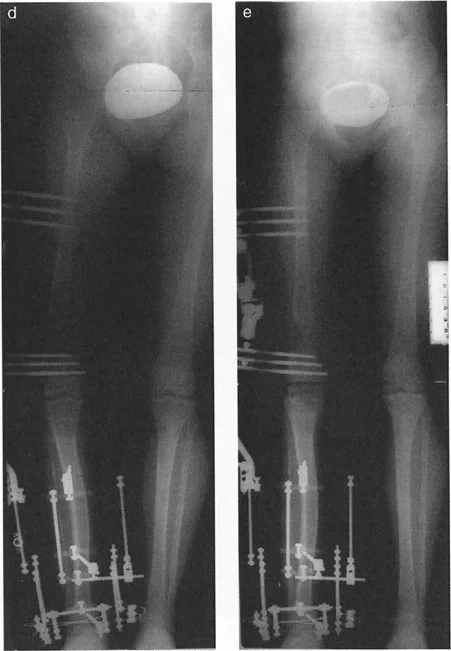

إتقان معدلات الشد: قاعدة المثلثات المتشابهة

القاعدة الذهبية البيولوجية لتوليد العظم بالشد، التي وضعها إليزاروف بعد عقود من التجارب على الحيوانات والبشر، هي معدل شد يبلغ 1 ملم يوميًا. يتم تقسيم هذا عادة إلى زيادات قدرها 0.25 ملم كل 6 ساعات لمحاكاة النمو المستمر للوحة النمو.

ومع ذلك، فإن الخطأ الشائع، الذي قد يكون كارثيًا أحيانًا للجراحين المبتدئين، هو سوء فهم أين يجب أن يحدث هذا الـ 1 ملم يوميًا.

معدل 1 ملم/يوم ينطبق بشكل صارم على القشرة المقعرة للعظم في موقع قطع العظم (الحافة الأمامية للإسفين المفتوح). نظرًا لأن الجهاز (قضيب الشد أو دعامة TSF) يقع على مسافة من العظم، خارج غلاف الأنسجة الرخوة، فإنه يتحرك على طول قوس أكبر بكثير. إذا وجهت المريض لشد القضيب بمعدل 1 ملم يوميًا، فإن العظم الفعلي سيُشد بجزء ضئيل من هذا المعدل، مما يؤدي إلى التصلب المبكر لموقع قطع العظم.

حساب معدل الشد الحقيقي

لحساب المعدل الصحيح للشد عند المفصلة، نستخدم قاعدة المثلثات المتشابهة، والتي تعتمد أساسًا على القاعدة الهندسية للدوائر متحدة